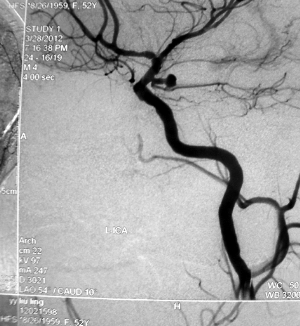

山东大学齐鲁医院神经外科杨扬教授是我国较早开展神经介入放射技术的青年神经病临床医学专家。他专门从事我国神经医学的发展、学术研究和国际学术交流工作,把全部精力都投入到神经介入医学的临床教育事业中;他努力跟踪国外先进技术,善于将临床试验与科学研究相结合,在脑与脊髓血管病发病机制、神经解剖基础研究、血液动力学、疾病分类以及栓塞材料的研制和改进等方面取得了丰硕的成果。在他和同行的共同努力下,我国神经病学科成就引起了国内外医学界的广泛重视,其中多项成果被国际医学界推广应用;他在学术研究方面成果突出,还应邀到国际会议上讲学……8+6\', 百拇医药

杨扬教授:我们学科的传统强项是脑血管搭桥显微血管吻合技术,并为后来在山东省率先开展颅内外低流量搭桥治疗烟雾病,及高流量搭桥手术治疗颅内复杂动脉瘤手术奠定了基础;更重要的是,当初刻苦练就的显微血管缝合技术也为今天的颅内复杂动脉瘤夹闭—血管搭桥—神经介入全方位协同治疗模式奠定了基础。这也确是“始料不及”的意外惊喜吧。1n, http://www.100md.com

杨扬教授:有世界公认最凶险的颅内动脉瘤―基底分叉动脉瘤夹闭手术,将我们学科中断了20多年的脑血管搭桥技术加以继承;还开展了颅内外低流量搭桥治疗烟雾病,及高流量搭桥手术治疗颅内复杂动脉瘤手术;经小脑延髓裂入路手术;枕下远外侧经髁入路手术;乙状窦前入路岩骨部分切除―回植手术。1n, http://www.100md.com

神经外科的手术经验和技巧都是实践中磨练出来的。杨扬教授从事“神外”临床已经25年,长期的手术经验技术积累使他对各种脑科手术游刃有余,不仅熟练掌握各种颅内外科疑难杂症的治疗,更是对脑血管搭桥术、颅内动脉瘤开颅夹闭及介入神经外科手术有着十分丰富的临床经验。$u, 百拇医药

杨扬教授为临床技能型医师,专业特长:1.脑血管外科。擅长脑血管显微外科技术:包括颅内动脉瘤、脑血管搭桥、动静脉畸形、颈动脉内膜剥脱等手术及神经介入治疗技术。2.颅底外科(脑膜瘤、垂体腺瘤、颅咽管瘤、听神经瘤等)手术。杨扬教授在国际神经病学权威杂志发表SCI收录论文3篇,内容均为临床实用技术。$u, 百拇医药

杨扬教授继承并不断完善齐鲁医院神经外科的传统强项——脑血管搭桥显微血管吻合技术,为后来在山东省率先开展颅内外低流量搭桥治疗烟雾病及高流量搭桥手术治疗颅内复杂动脉瘤手术奠定了基础。他为神经介入做技能培训,为颅内复杂动脉瘤夹闭—血管搭桥—神经介入全方位协同治疗模式奠定基础。杨扬教授先后在数十个人体解剖头颅标本上进行过神经外科局部解剖手术模拟练习,为临床上完善颅底外科手术技术奠定了基础。他参加了2008年卫生部认证的内镜规范化培训,获得全国神经内镜使用资格证书,并在临床上开展了神经内镜辅助微创手术。$u, 百拇医药

杨扬教授在国内外有影响力的临床特色技术有:1.硬膜外前床突切除视神经减压手术方式:有关论文已在神经病学科国际高级别刊物《Neurosurgery》上发表,这标志着山东齐鲁医院神经外科在国内外颅底外科领域拥有了无可争议的地位;2.神经导航系统下辅助三叉神经射频卵圆孔穿刺技术:相关论文已经发表在国际影响力的杂志《The Clinical Journal of Pain》上,并引起了世界知名专家的关注;3.纵裂入路胼胝体开窗技术:杨扬教授在临床上的治疗思路受到国际知名专家的认可,这种完全独立开发的全新手术方式,在我国神经外科史上可谓独创。论文已在国际神经外科知名杂志《World Neurosurgery》上发表。4.线锯穿过眶下裂的额颞眶颧开颅技术:克服了传统额颞眶颧开颅中眶下裂难以定位的问题,明显简化了手术步骤。论文发表在国内神经病学科非常具影响力的《中华神经外科杂志》上。$u, 百拇医药

有人戏称神经外科医生是“和神并驾齐驱的医生”。杨扬这个“神外”医生拥有25年从业经历,这使他对各种脑科手术游刃有余。手术经验和技巧都是实践出来的。长期的技术积累,让杨扬不仅熟练掌握各种颅内外科疑难杂症的治疗方法,更是积累了十分丰富的脑血管搭桥术、颅内动脉瘤开颅夹闭及介入神经外科手术经验。$u, 百拇医药

杨扬教授每年诊断治疗神经介入手术例数上百例,他继承并完善了齐鲁医院神经外科的传统强项——脑血管搭桥显微血管吻合技术,为后来在山东省内率先开展颅内外低流量搭桥治疗烟雾病,及高流量搭桥手术治疗颅内复杂动脉瘤手术奠定了基础。杨扬教授在山东省内率先开展了多项高难度、高风险手术,包括世界公认最凶险的颅内动脉瘤——基底分叉动脉瘤夹闭手术。他医风严谨,完全从临床实用知识理论和技能的研究出发,理论联系实际,建立了显微神经外科局部解剖及手术技能培训实验室,推出多项临床新技术,在专业领域里不断做出新贡献。$u, 百拇医药